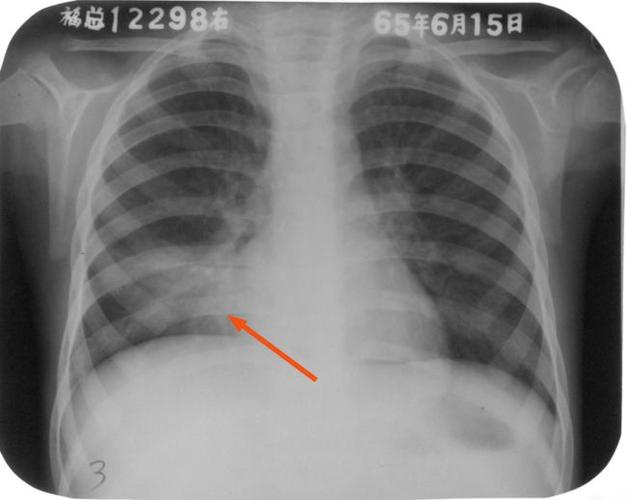

大叶性肺炎x光片,大叶性肺炎胸片

右中叶实变右上肺可见大片状实变影,以叶间裂为分界图1 右上叶大叶性